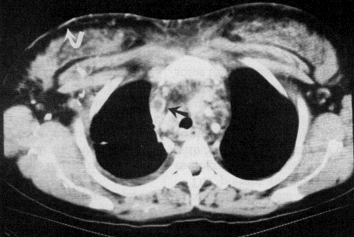

Şəkil 10. KT. Kontrastın qida borusundan ekstravazasiyası

Endoskopiyadan sonra emfizemanın ortaya çıxması, oral kontrastlı rentgendə və ya KT-də kontrast ekstravazasiyası qida borusu perforasiyasını göstərən əlamətlərdir (Şəkil 11).